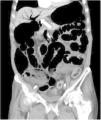

An 81-year-old man with a history of type 2 diabetes mellitus was admitted to our hospital because of abdominal bloating. He had started taking voglibose six days earlier. Physical examination showed abdominal distension, but no abdominal tenderness. Contrast-enhanced abdominal computed tomography revealed an expanded intestinal tract and portal emphysema (Fig. 1). Voglibose was suspended, and the patient underwent emergency laparotomy for suspected non-occlusive mesenteric ischemia. However, there were no signs of intestinal necrosis or perforation (Fig. 2). Bowel decompression was then performed. Computed tomography was carried out on the seventh day of hospitalization, showing no portal emphysema (Fig. 3), and oral diet was started on day 10. The patient’s clinical course was uneventful, and he was transferred to a long-term care hospital on day 24. Portal venous gas has been known to be a rare complication in patients taking alpha-glucosidase inhibitors (α-GIs) and could result from pneumatosis cystoides intestinalis, rather than intestinal ischemia.1,2 It can be managed conservatively, and unnecessary surgical treatment should be avoided.